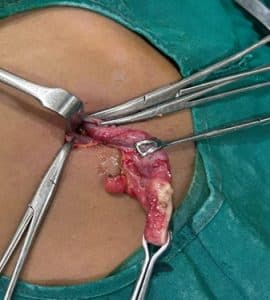

Appendix was found to be in stage 4-perforated with abscess and gangrene formation. An open appendectomy and lavage were performed. Intraoperative findings showed an appendix that was found to be inflamed and gangrenous, with subhepatic perforation and abscess formation. (even though there was no air under the diaphragm on scanning). Pus was sent for culture and sensitivity, and the appendix specimen (figure 10) was sent to pathology. Revealed subhepatic appendicular perforation with gangrene and abscess formation.

Figure 10: Appendix specimen sent to pathology